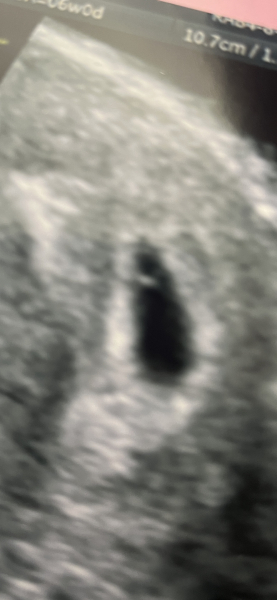

This is what mine was like at 6 weeks, I have another next week when 8 weeks. Not sure if helpful? Looked like a ring

4-5weeks pregnant